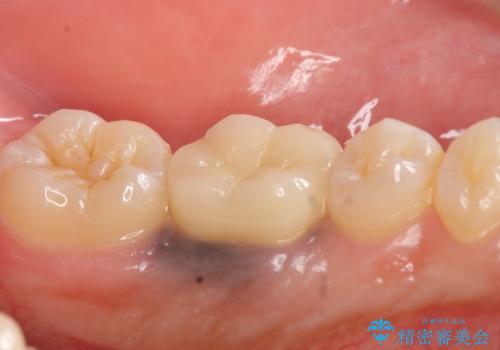

今回用いたオールセラミッククラウンはジルコニアフレームという白い素材の上にセラミックを盛っているため、審美性が非常に高いのが特徴です。

また、ジルコニアは人工ダイヤモンドの材料にも使われているほど高い強度を持っており、そのためオールセラミッククラウンは審美性だけでなく、奥歯やブリッジの補綴も可能とするクラウンです。